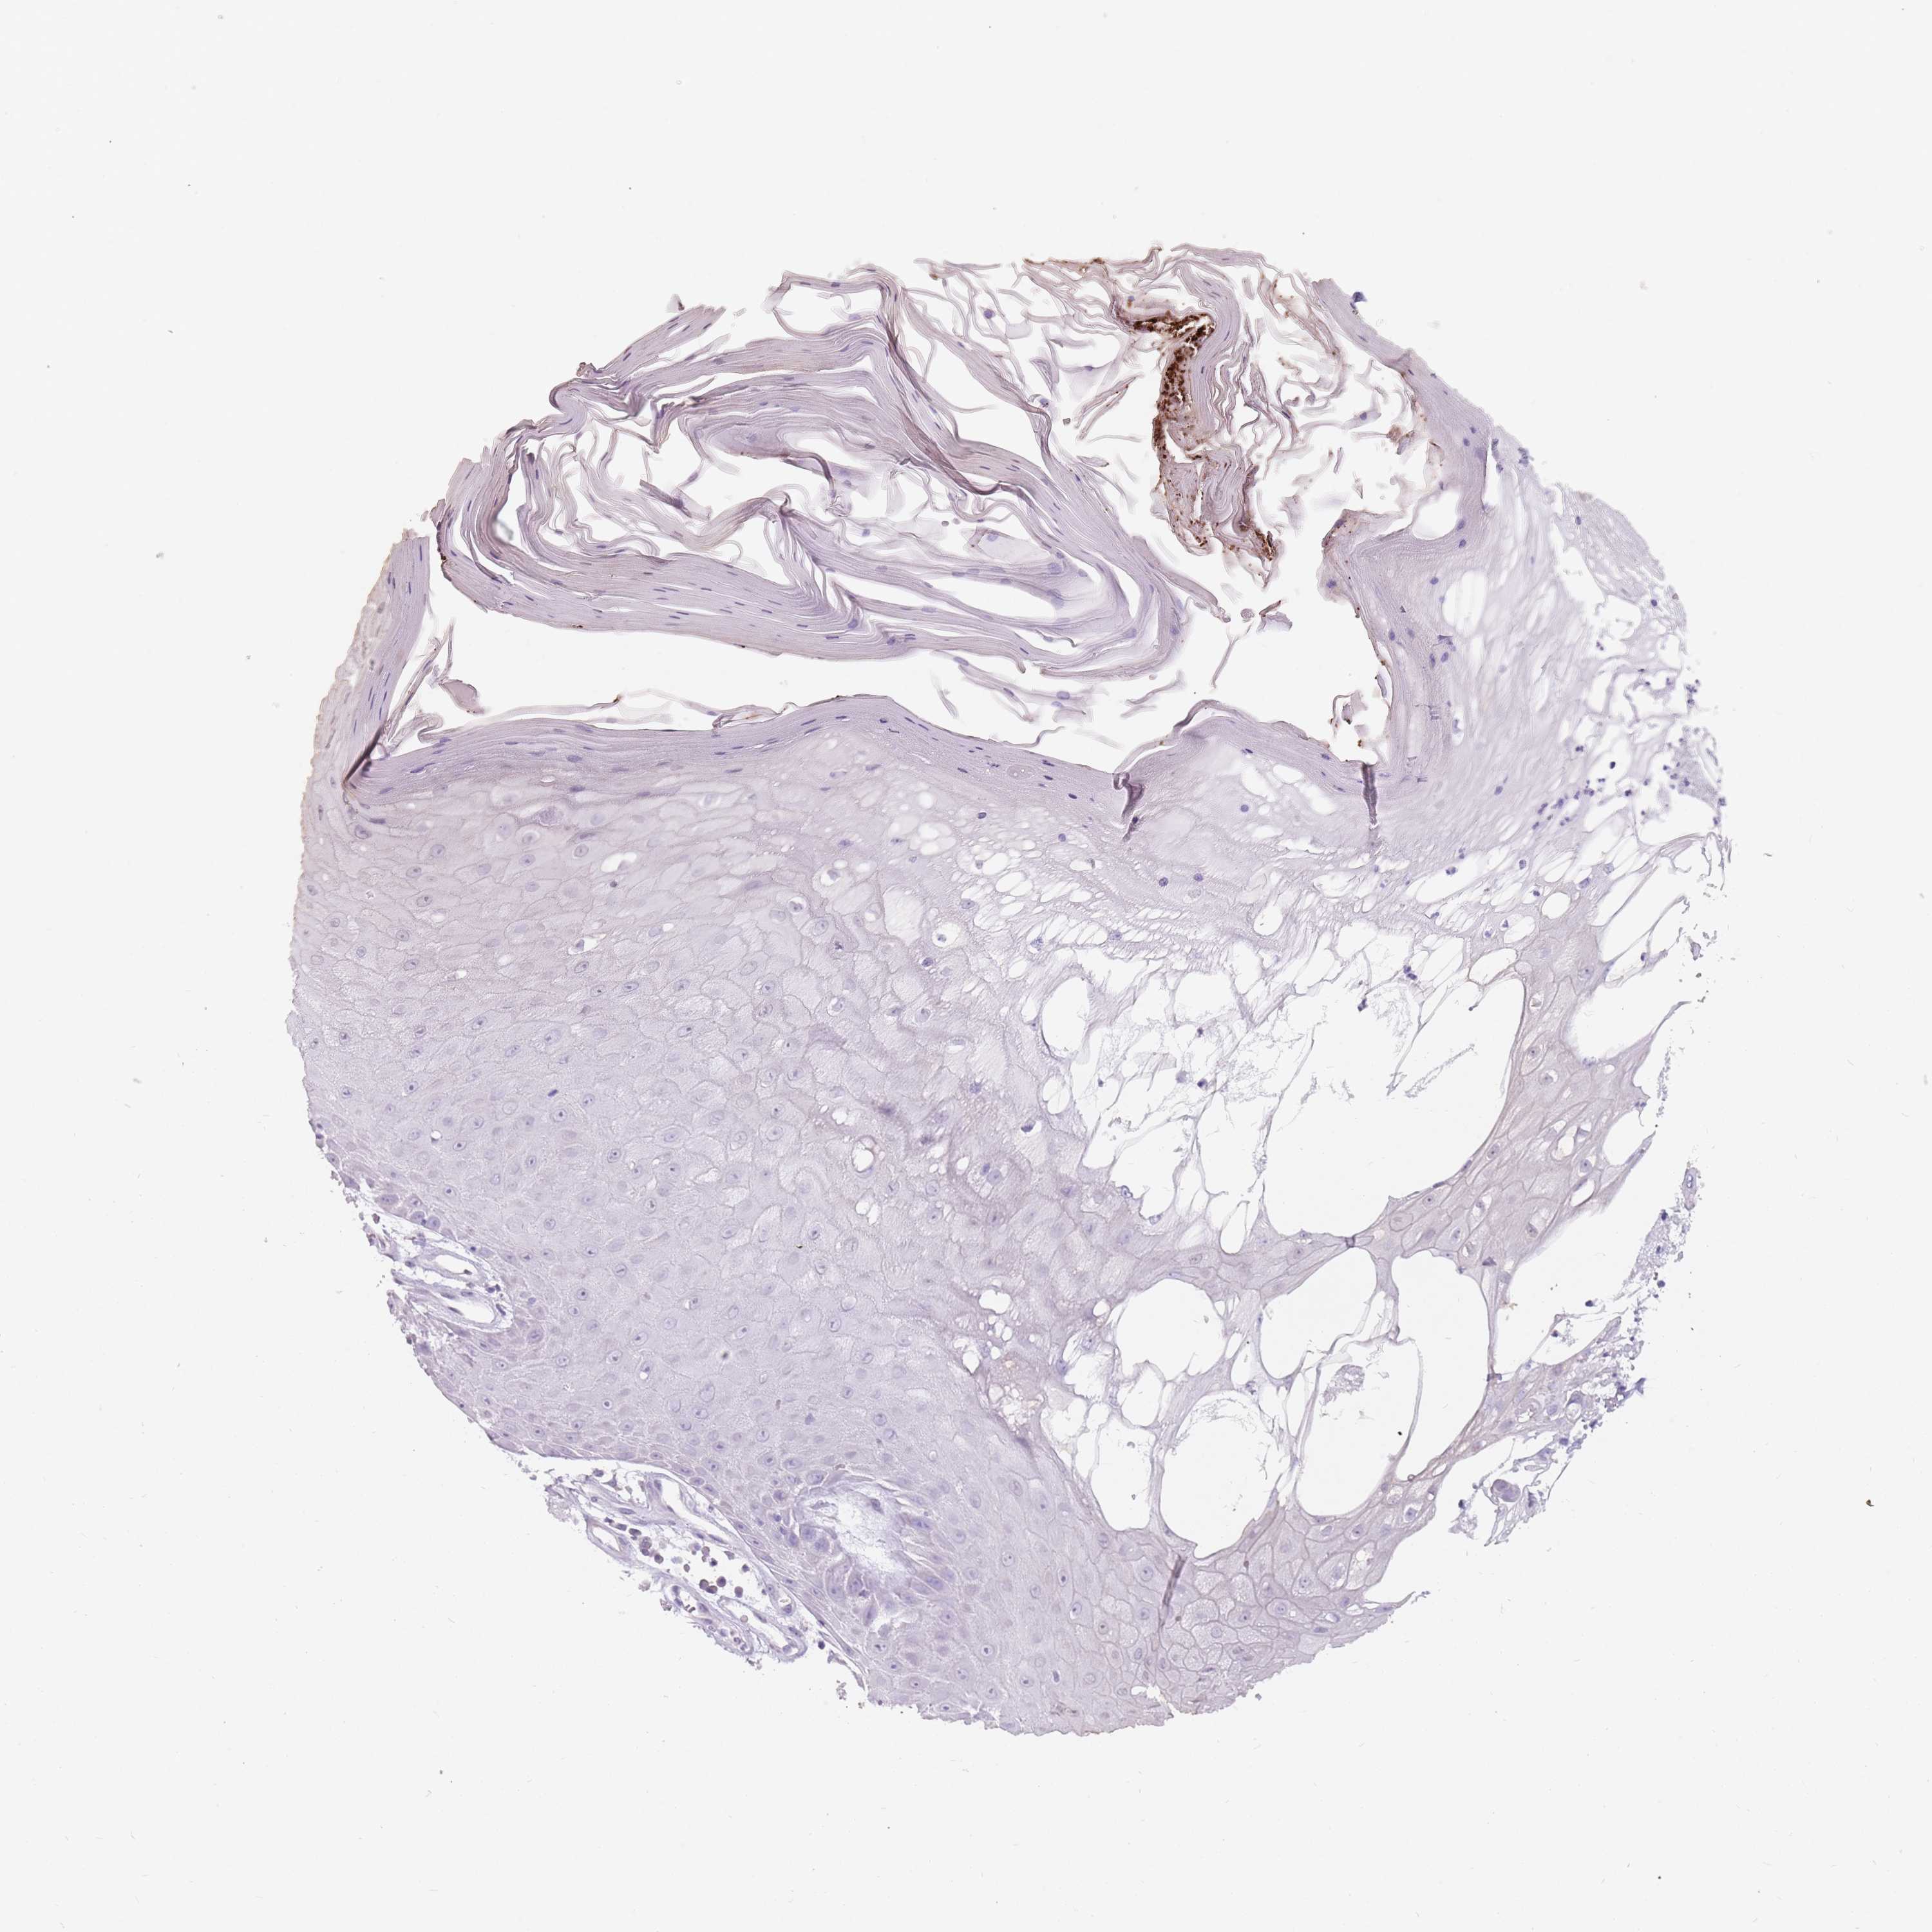

SKIN CANCER - Protein expressioni

A mouse-over function shows sample information and annotation data. Click on an image to view it in a full screen mode. Samples can be filtered based on level of antibody staining by selecting one or several of the following categories: high, medium, low and not detected. The assay and annotation is described here.

Antibody stainingi

Antibody staining in the annotated cell types in the current human tissue is reported as not detected, low, medium, or high, based on conventional immunohistochemistry profiling in selected tissues. This score is based on the combination of the staining intensity and fraction of stained cells.

Each image is clickable and will lead to virtual microscopy that enables deeper exploration of all samples and also displays staining intensity scores, fraction scores and subcellular localization as well as patient and tissue information for each sample.

Antibody CAB026170

Squamous cell carcinoma, metastatic, NOS

Squamous cell carcinoma in situ, NOS

Squamous cell carcinoma, NOS